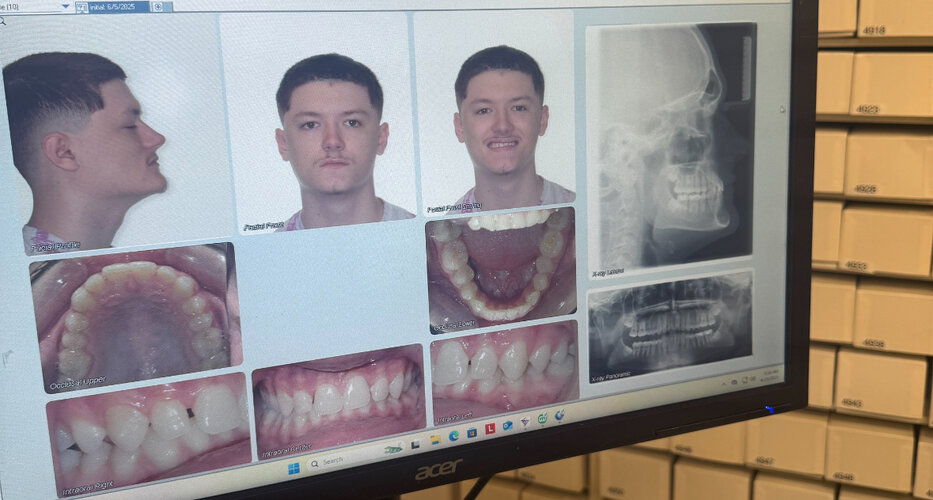

My friend has perfect chin projection but has a very bad deep bite from my understanding this usually recesses the chin? So would it protrude the chin more when corrected or line the face up increasing harmony